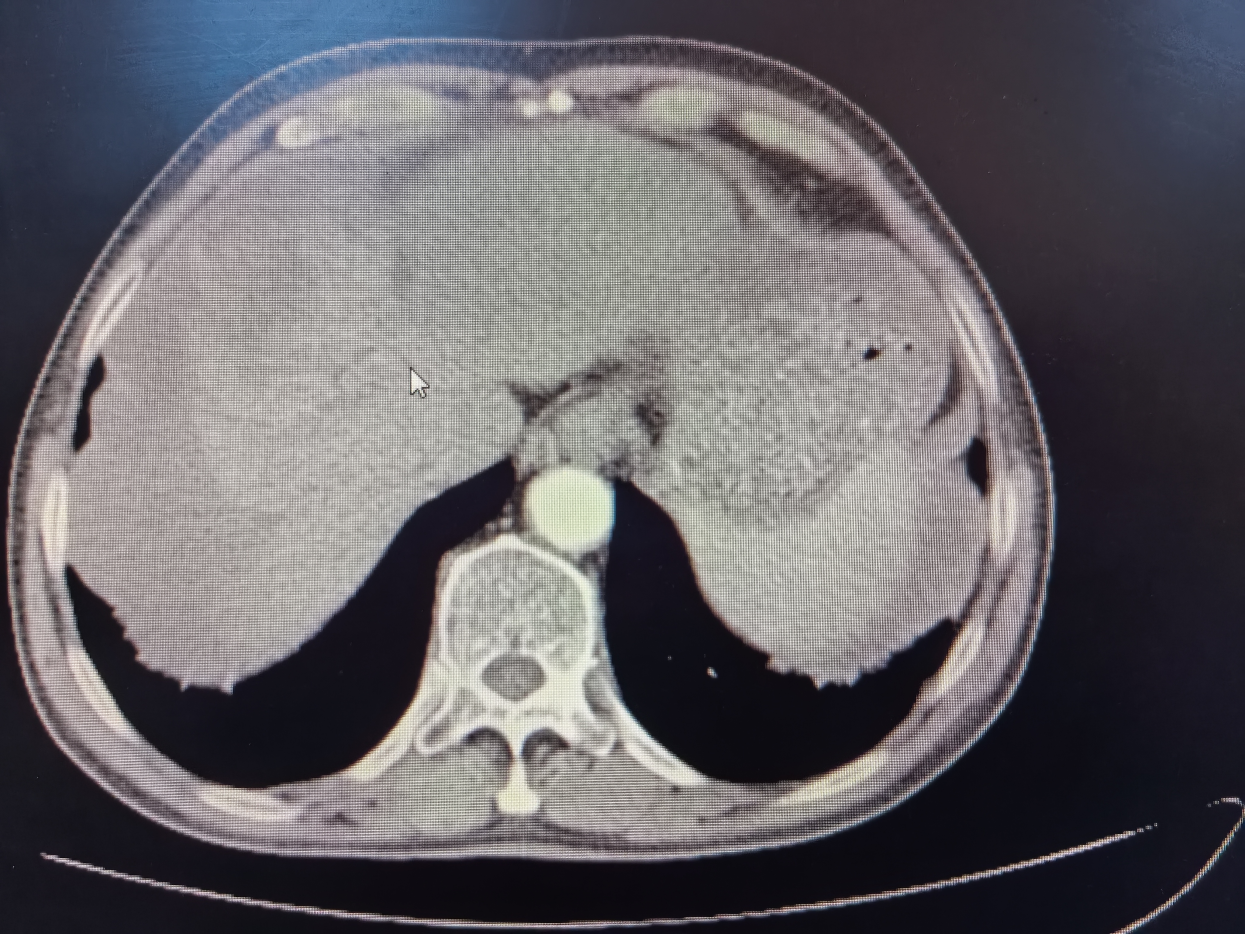

介入治療由肝膽外科劉楊波副主任醫(yī)師主刀,通過精準(zhǔn)的血管置管定位,采用化療藥物對腫瘤進(jìn)行局部灌注治療。經(jīng)過兩個周期的介入治療,規(guī)律口服靶向藥后,候先生的腫瘤體積明顯縮小,由原來的9.0cm縮小至7.0cm,且腫瘤邊界清晰,無大血管侵犯,周邊子灶已無活性,達(dá)到了預(yù)期的治療效果,成功由臨床不可切除肝癌轉(zhuǎn)化可切除肝癌。患者再入院后,肝膽外科手術(shù)團(tuán)隊隨即為候先生制定了詳細(xì)的肝切除手術(shù)方案。手術(shù)當(dāng)天,蔣水平博士和劉楊波、薛文副主任醫(yī)師組成的手術(shù)團(tuán)隊成功在腹腔鏡下切除了患者體內(nèi)的肝臟腫瘤。術(shù)后,候先生恢復(fù)良好,影像檢查提示局部未見腫瘤和轉(zhuǎn)移征象,腫瘤指標(biāo)恢復(fù)正常,標(biāo)志著手術(shù)取得了圓滿成功。

術(shù)前 CT